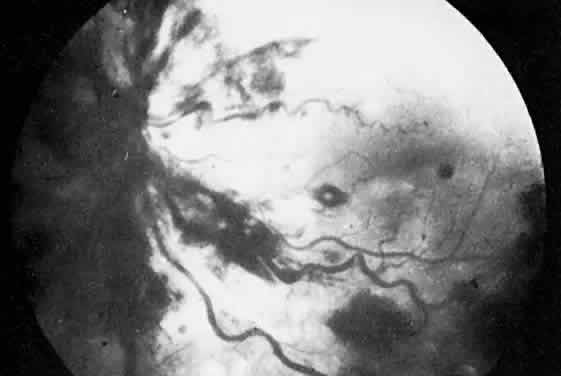

The ocular manifestations of antiphospholipid antibodies include retinal venous and arterial occlusions, amaurosis fugax, diplopia, and visual field loss.34,35 Extensive vasoocclusion, neovascularization, and vitreous hemorrhage may occur (Fig. 3). Treatment consists of photocoagulation for the neovascularization and systemic anticoagulation and immunosuppression. Vitrectomy may be required for vitreous hemorrhage. The role of systemic treatment of lupus anticoagulant in the management of ocular disease is unclear. Some investigators suggest that systemic anticoagulation be started promptly.36 The optimal duration of anticoagulation and whether antiplatelet therapy should be used are not known however. The optimal use of corticosteroids or other immunosuppressive drugs such as cyclophosphamide and azathioprine also is unknown. Two reports have found an association with the antiphospholipid syndrome and some additional retinal conditions. One report also has associated the primary antiphospholipid syndrome with central serous chorioretinopathy.37 In addition, lupus anticoagulant positivity could represent an additional risk factor for diabetic retinopathy according to a recent report.38

Fig. 3. Retinopathy associated with lupus anticoagulant with disc neovascularization and vitreous hemorrhage. (Kleiner RC, Najarian LV, Schatten S et al: Vaso-occlusive retinopathy associated with antiphospholipid antibodies [lupus anticoagulant retinopathy]. Ophthalmology 96:898, 1989.)